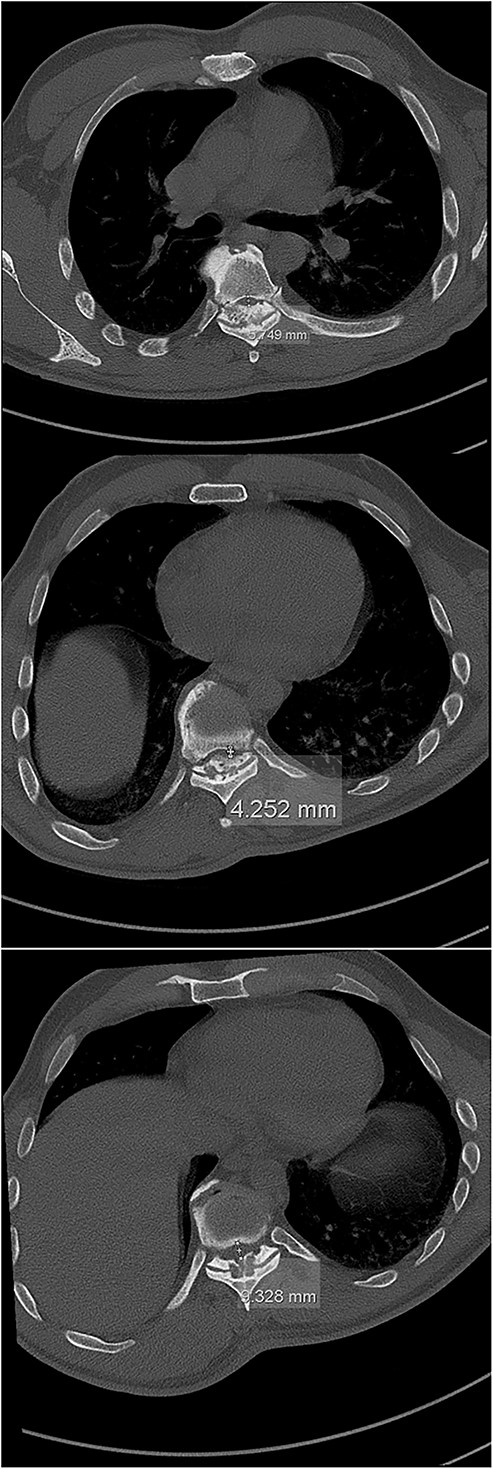

The imaging studies revealed thoracic kyphoscoliosis (with a kyphotic curve of 50°, left upper-thoracic curve of 40° and right lower-thoracic curve of 25°) and significant stenosis of the thoracic part of the spinal canal (particularly at levels Th6, Th9 and Th11) due to severely ankylosed ligamentum flavum (OLF) and the concomitant degeneration of the facets (Figs 1 and 2). Imaging indicated thoracic myelopathy (Fig. 3). We performed emergent posterior wide laminectomy using an ultrasound bone scalpel, and a partial correction of the deformity by instrumented spinal fusion (Th6-Th12). The surgery was performed by the senior author (N.H.).

The initial CT scan (axial views), showing the width of the spinal canal at Th6 (above), Th9 (middle) and Th11 (below).

In up to 51% of patients in need of decompression surgery due to thoracic myelopathy, the presence of the OLF was noted, whereby the prominent clinical feature in these patients was the deficit in vibratory sensation and proprioception on account of the compressed dorsal spinal cord [2, 5, 8]. The numbness was also present in our patient, along with significant pain and acute aggravation of paraplegia. The most prevalent location of OLF is the lower thoracic spine with the highest peak being at Th10-12 (and the second highest at Th3-5, respectively), whereby the ossification of the other spinal ligaments can accompany OLF [1, 3, 9]. This was also observed in our case, where the most significant spinal stenosis was also observed in lower thoracic segments (namely Th6, Th9 and Th11).

Computed tomography (CT) is considered the most useful diagnostic imaging modality in identifying the ossification of the spinal ligaments, including the OLF [3, 8]. In severe cases, the ossification can also include the dorsal area of the dura, making the surgical treatment of the OLF very challenging, with a high risk of a dural compromise and leakage of the cerebrospinal fluid [2, 5, 8, 10]. However, this was not the case with our patient.